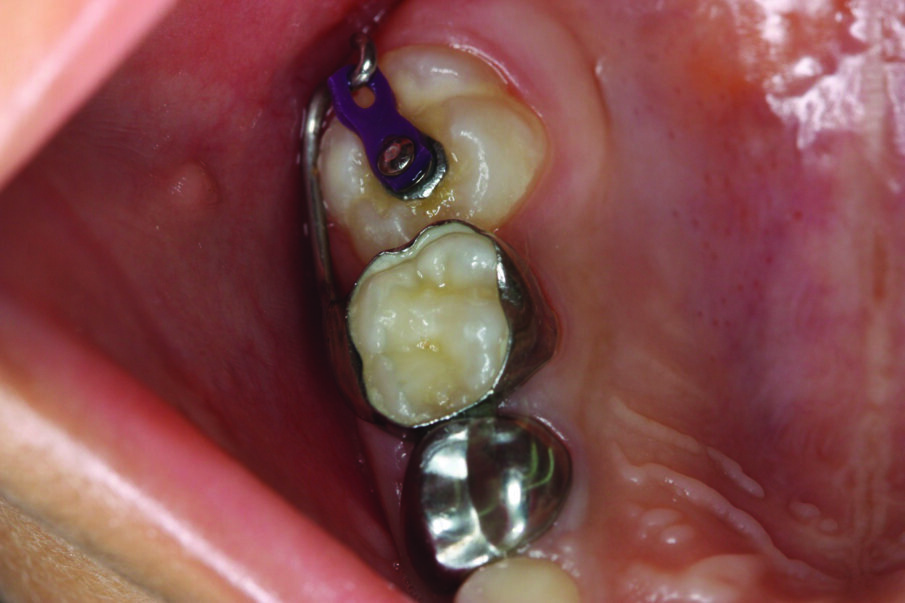

Figure 3: A plastic orthodontic separator is placed to attempt to correct a mild ectopic eruption in the upper right first permanent molar.

Treatment depends on how severe the impaction appears clinically and radiographically. For mildly impacted first permanent molars, where little of the tooth is impacted under the primary second molar, elastic or metal orthodontic separators can be placed to wedge the permanent first molar distally4, Figure 3. For more severe impactions, distal tipping of the permanent molar is required. Tipping action can be accomplished with brass wires, removable appliances using springs, fixed appliances such as sectional wires with open coil springs, Figure 4, sling shot-type appliance3, Figure 5, a Halterman appliance5, Figure 6, or surgical uprighting6.